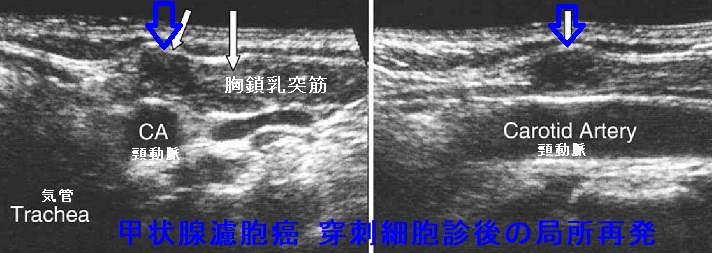

甲状腺乳頭癌の穿刺経路再発(穿刺細胞診後再発、Needle tract implantation、Needle tract seeding)

甲状腺穿刺細胞診後再発(穿刺経路再発、Needle tract implantation、Needle tract seeding)は穿刺経路に残った癌細胞が増殖したものです。甲状腺穿刺細胞診後再発(穿刺経路再発)

1. 甲状腺癌穿刺後5年で0.15%、10年で0.37%の頻度

2. 転移リンパ節穿刺後5年で0.37%、10年で0.58%の頻度

3. 53%の患者で元の癌よりも悪性度が高い組織型になる

4. 再発ない場合に比べて予後が悪くなる

[World J Surg. 2020 Feb;44(2):378-384.]

甲状腺乳頭癌の穿刺経路再発 超音波(エコー)画像

甲状腺乳頭癌の甲状腺穿刺細胞診後再発(穿刺経路再発) 超音波(エコー)画像

甲状腺乳頭癌の穿刺経路再発 超音波(エコー)画像 エラストグラフィー

甲状腺乳頭癌の甲状腺穿刺細胞診後再発(穿刺経路再発) 超音波(エコー)画像 エラストグラフィー青く見えます(硬い)

甲状腺乳頭癌の穿刺経路再発(拡大) 超音波(エコー)画像

甲状腺乳頭癌の甲状腺穿刺細胞診後再発(穿刺経路再発) 超音波(エコー)画像(拡大)

甲状腺乳頭癌の穿刺経路再発 超音波(エコー)画像(拡大) ドプラーモード

甲状腺乳頭癌の甲状腺穿刺細胞診後再発(穿刺経路再発) 超音波(エコー)画像(拡大) ドプラーモード

甲状腺濾胞癌の局所再発

甲状腺濾胞癌の局所再発は、切除手術での遺残だけでなく、甲状腺穿刺細胞診後再発(穿刺経路再発)もあります。また、稀ながらリンパ節転移・リンパ節再発する場合もあります。甲状腺濾胞癌の特殊型 甲状腺濾胞癌(好酸性細胞型、膨大細胞癌)ではリンパ節転移・リンパ節再発が主です。

甲状腺濾胞癌穿刺細胞診後の局所再発(甲状腺穿刺細胞診後再発、穿刺経路再発)もあり得ます。穿刺経路に残った濾胞癌細胞の増殖によります。

下の写真は甲状腺濾胞癌摘出後5年して胸鎖乳突筋、肩甲舌骨筋内に発生した甲状腺濾胞癌です。(Surg Today. 2007;37(1):34-7.)

甲状腺濾胞癌 穿刺細胞診後再発